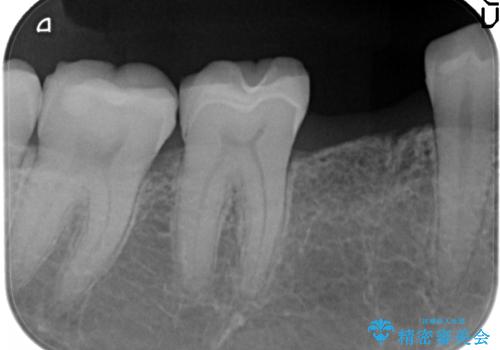

- 大人になっても残っていた乳歯が噛むと痛くなり、治療を求めて来院されました。

残す手段を検討しましたが大きな虫歯・根尖病変の存在し、大きく歯ぐきも腫れ炎症も強く認められる状態を改善するため抜歯を行いインプラントによる咬合機能回復を計画します。

大人になっても残っている乳歯は根管治療や他の治療で残せる場合もありますが、今回のように状態が悪い場合早期に抜歯をすることで歯槽骨が温存でき十分に安定した骨量でインプラントによる機能回復を達成することができました。